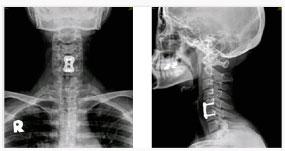

척추관 협착증의 방사선 소견

후방 요추체간 유합술 (PLIF) : 광범위한 후방 감압술 후 추간판(디스크)을 제거한 후 골이식을 시행하여 추체간 유합을 얻는 것

- 후외방 유합술에 비해 절개가 적다

- 신경근에 대한 충분한 감압이 이루어진다

- 추간판(디스크)로 인한 동통 및 재발이 없다

- 추간판 높이를 정상으로 회복시켜 준다

- 척추 정렬을 정상으로 회복시켜 준다

* 현재에는 최소 침습적인 방법으로 적은 절개를 통해 가능하다